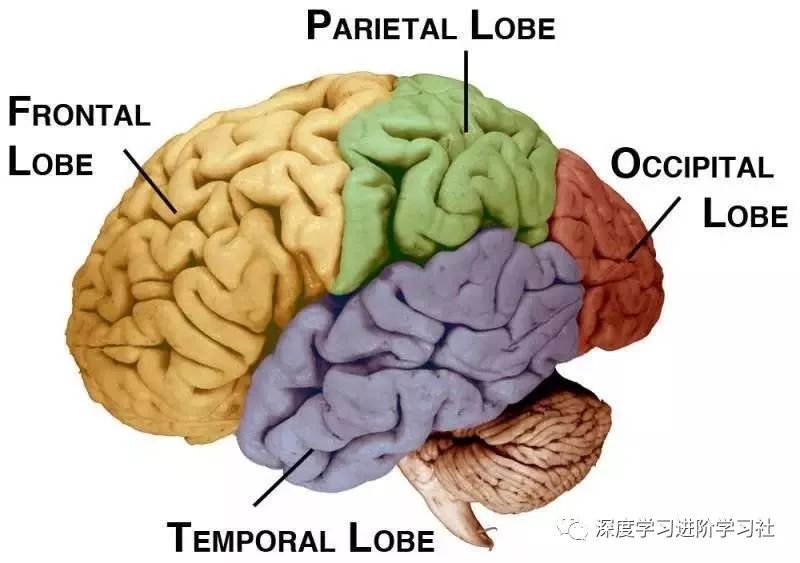

皮层(Cortex)

最后,我们到达了大脑皮层。

大脑皮层(本文主要指新皮层,文中统称皮层)基本上负责所有事情:看,听,触觉,语言,动作,思维,规划和个性。

它分为四叶(lobe):

它们每个都做了很多事情,且有很多重叠:

额叶(Front lobe)处理个性,以及我们认为的许多“思考”——推理、规划和执行能力。特别是,您的许多想法发生在额叶的前部,称为前额叶皮质。额叶负责你的身体运动。额叶的顶部条是您的主要运动皮质。

在其它功能中, 顶叶控制你的触觉,特别是在初级躯体感觉皮层。

运动和躯体感觉皮层紧挨着对方,它们很有趣,因为它们已经被良好的映射出来了。神经科学家确切地知道每个部分连接到你身体的哪一个部分。于是就有了下面这张令人毛骨悚然图:侏儒。

如果你把皮层从大脑中剥下来,你会得到一张2mm厚,2,000-2,400cm2 大小(48cm x 48cm square)的餐巾纸。

这块餐巾是大脑发生大部分动作的地方,这就是为什么你可以思考,移动,感觉,看,听,记,说话和理解语言。真是有史以来最好的餐巾纸。